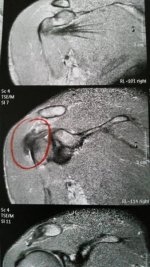

Auf den Bildern ist eine Sehne oder ein Band wohl verdickt!?

Können diese Schmerzen "alleine" daher kommen? Woher kann eine solche Verdickung kommen? Überbelastung, Fehlhaltung, muskuläre Dysbalancen ...?